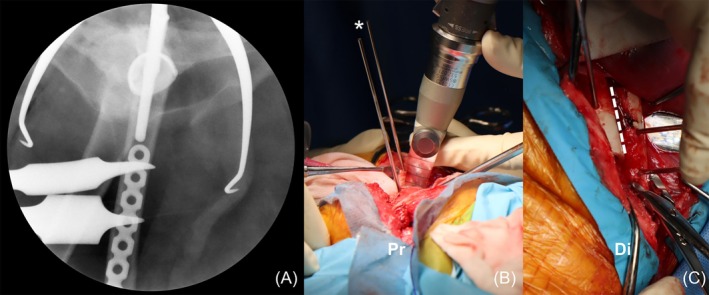

Methods: Standard THR was performed to alleviate pain and restore limb function. After confirming the prostheses were non-reducible, DFSO was performed as a novel tension-relieving technique at a level that allowed internal fixation. The shortening length was determined by the intraoperative tension required to reduce and maintain the prosthesis. Data from medical records were collected, including signalment, clinical signs, implant used, shortening length, and outcomes.

Results: Following DFSO, prosthesis reduction was successful in all dogs. The median femoral shortening length ratio was 13.8% (range, 10.7%-15.3%). One intraoperative complication involved a fissure of the greater trochanter, which occurred during trial reduction before DFSO. Median duration of follow-up was 21 months (range, 3-34 months). Two dogs showed good to excellent limb function. Bone union was consistently achieved in all DFSO procedures. Two postoperative complications were observed: one case of prosthesis luxation and one case of aseptic stem loosening. The owner declined revision surgery for luxation, and explantation was performed for the stem loosening.